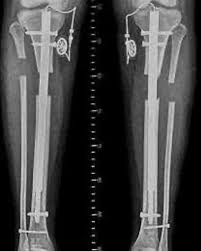

Estabilização óssea temporária ou definitiva com fixadores externos, placas ou hastes conforme a necessidade clínica.

Reconstrução de falhas ósseas extensas após erradicação da infecção.

Os resultados clínicos com essa abordagem integrada incluem maior taxa de controle da infecção, recuperação funcional e redução significativa das recidivas.